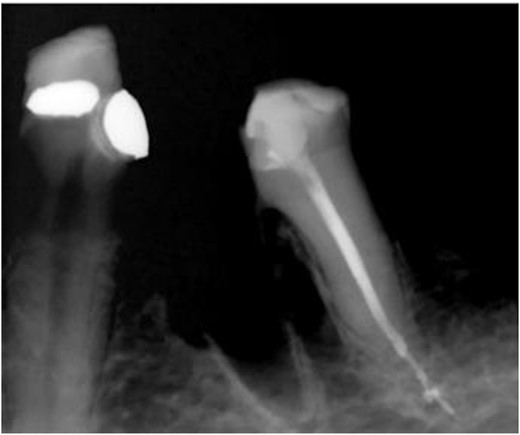

After removal of the existing restoration and caries, the cavity margin on the mesial side was noted to be 1 mm subgingival, with a mid-palatal margin extending to the root surface. Non-surgical root canal treatment was performed under local anesthesia and rubber dam isolation. Only the DB and DL canals were cleaned and shaped, and obturation was completed using ProTaper Gold gutta-percha with AH Plus sealer (Dentsply, Konstanz, Germany) (Fig. 8).

Periapical radiograph of tooth 36 with obturation on DB and DL canal. Sealer extrusion noted.